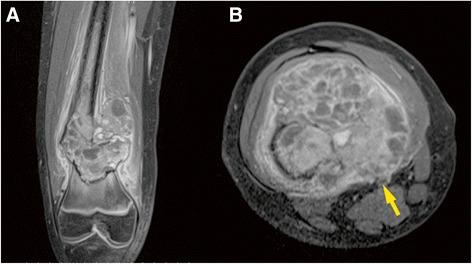

We present a 10-year-old girl who underwent limb-sparing surgery for a distal femur osteosarcoma. The femoral defect was 15 cm long, and the femoral vessel defect was 10 cm long. The femur was reconstructed with bilateral FVFG, and the femoral vessels were reconstructed with saphenous vein grafts. The grafts survived without vascular compromise, and the affected limb was preserved successfully.

Combined use of bilateral FVFG and autologous vein grafts makes limb-sparing surgery for a large osteosarcoma of the femur possible.